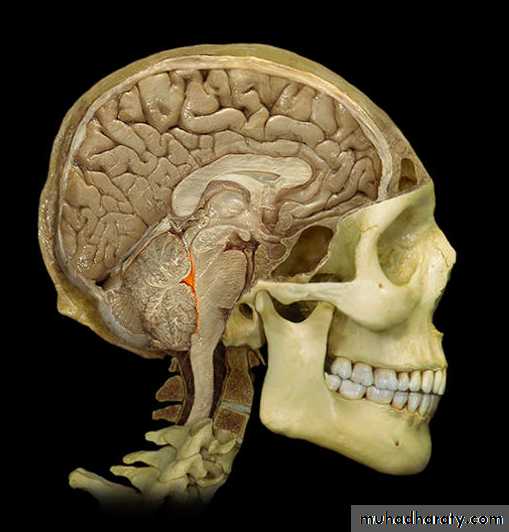

The Choroid Plexus

Choroid Plexus

• Choroid plexushang from the

roof of each

ventricle

• These plexuses

• form CSF

• The plexuses are

• clusters of thin

• walled capillaries

• enclosed by a

• layer of

ependymal cells

3rd Ventricle

• It lies below the lateral ventricles.

• It is a cavity of the diencephalon. In the roof there is

choroid plexus, that produce CSF.

4th Ventricle

It is a cavity of the rhombencephalon• It has a roof and floor.

• The floor is formed by two parts, medullary & pontine part.

• The roof formed by cerebellum

• It has 3 foramina, one is median (foramen of Magendie) located posteriorly and two are lateral (foramina of Lushka)